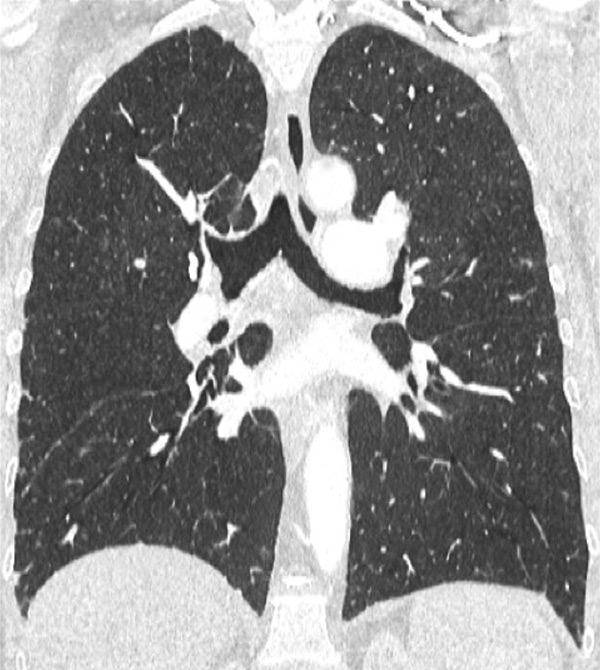

Figure 7

Portopulmonary hypertension in a 16-year-old. No abnormalities were found on morphological computed tomography (A/B), but heterogeneous perfusions were present on the perfusion map (stars, C/D).